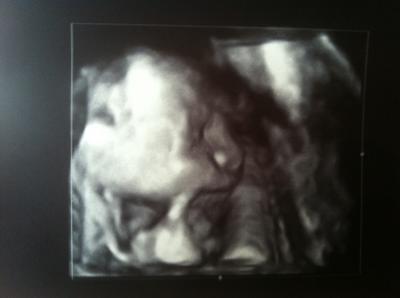

Ich bin gerade so Mega glücklich und erleichtert:) Es gab absolut keine Auffälligkeiten.. Der kleine Prinz ist ganz prächtig entwickelt:) bin heute 23+0 also 24. Woche:) der kleine ist 28cm groß und wiegt 600g man hat der sich entwickelt:-) Ich bin richtig stolz auf den kleinen Wurm.. Hier noch ein Bild wer genau hin sieht,erkennt alles:) Sieht aus als wenn er nuckelt :-))

Wie entspannt er da schaut ,total süß :)

Das freut mich das alles in ordnung ist. Hab auf dem bildchen dein prinzen erkennen können und den finger im mund :o) Wow echt wahnsinn wie gross er schon ist